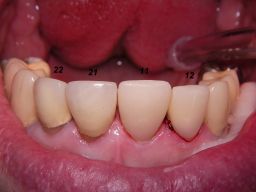

Links das Kontrollfoto nach der Sitzung am 17.2.06. Damit war die Vorbehandlung in diesem Fall abgeschlossen. Am 28.2.06 erfolgte die endgültige Präparation (das "Beschleifen") aller 4 Zähne. Links das Modell, auf dem die Kronen gefertigt worden waren. Rechts kurz vorm Zementieren der Kronen am 13.3.06. Aus der Längendifferenz der Zähne rechts und links kann man darauf schließen, daß die Präparation tief unter dem Zahnfleisch erfolgen mußte.

Links die Kronen aus dem Dentallabor "Heitmeyer Zahntechnik", Osnabrück. Man sieht praktisch keinen Metallrand. Der Patient war zur Farbbestimmung im Dentallabor - so halten wir es praktisch immer. Rechts das Ergebnis bei der 1. Nachkontrolle am 27.3.05. Das Zahnfleisch muß sich noch etwas erholen.